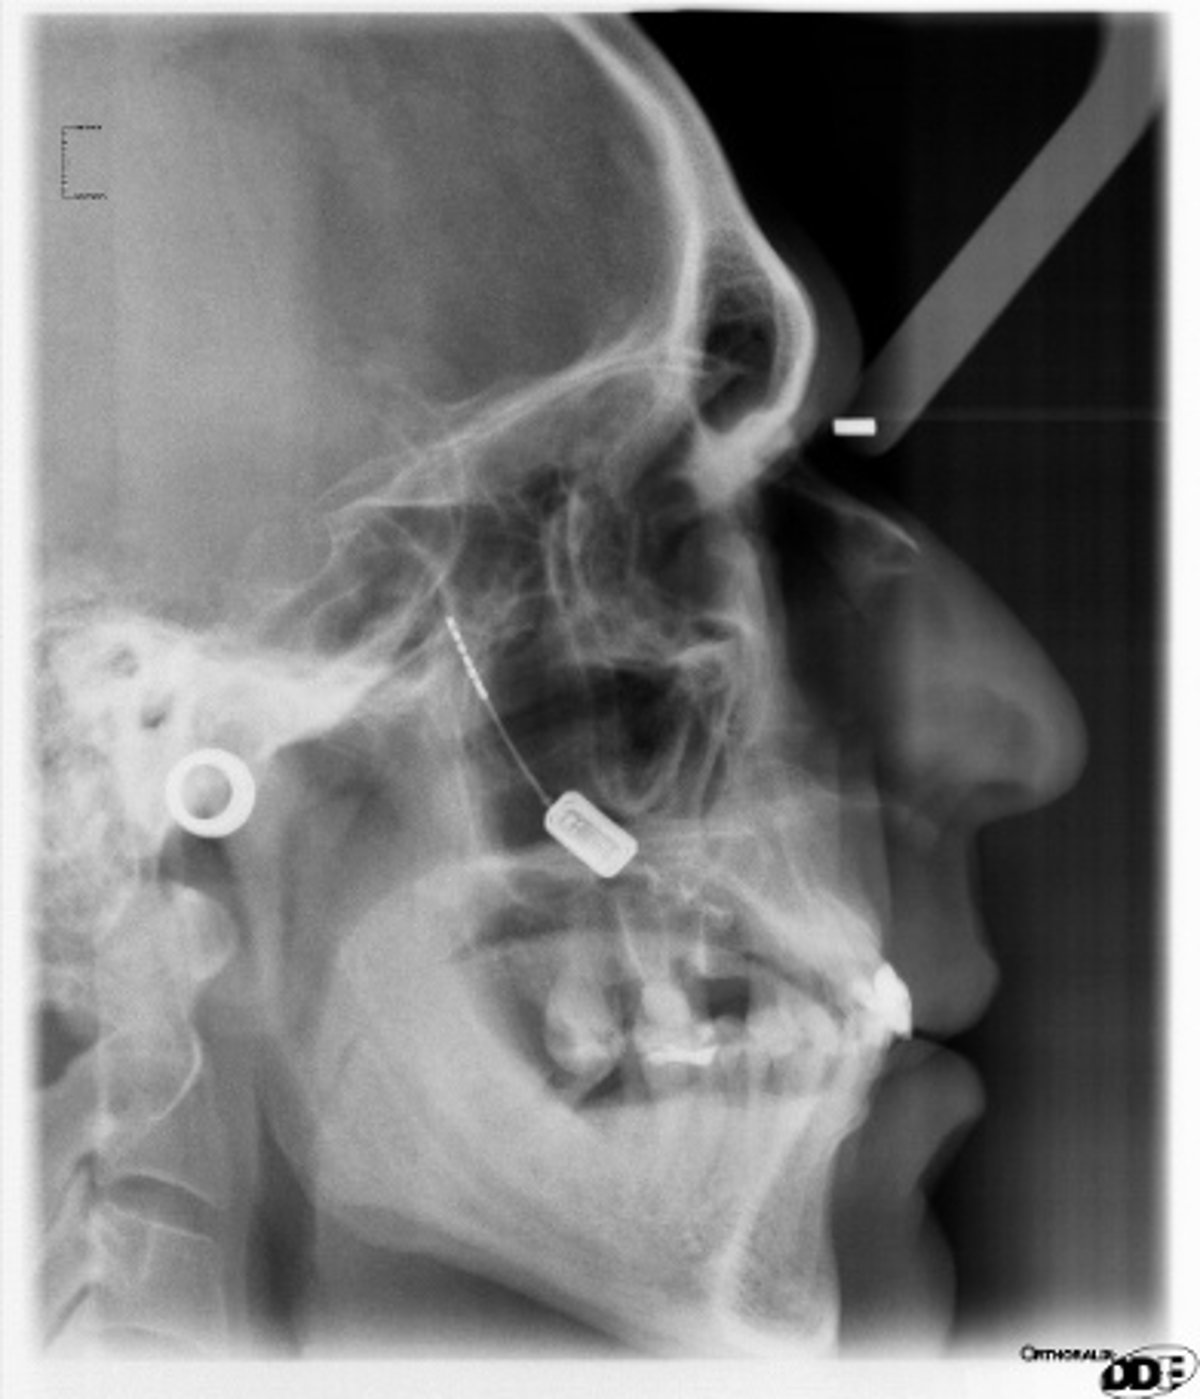

La técnica que se está probando consiste en la implantación de un pequeño dispositivo/neuroestimulador en el maxilar superior del paciente que produce una pequeña descarga, imperceptible para el paciente, que estimula un ganglio (esfenopalatino) y termina con el ataque de dolor.

El paciente dispone de un aparato, un pequeño mando, que, cuando comienza a notar los síntomas que le conducen a un dolor agudo de cabeza, presiona sobre el dispositivo instalado en el maxilar para producir dicha descarga eléctrica.